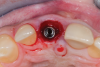

Fig 7. Finalized preparation utilizing the PET protocol, with implant placement in the No. 8 (1:1) position. An “S”-shaped chamfer preparation was made internally to the retained buccal portion of the root.

Figure 7